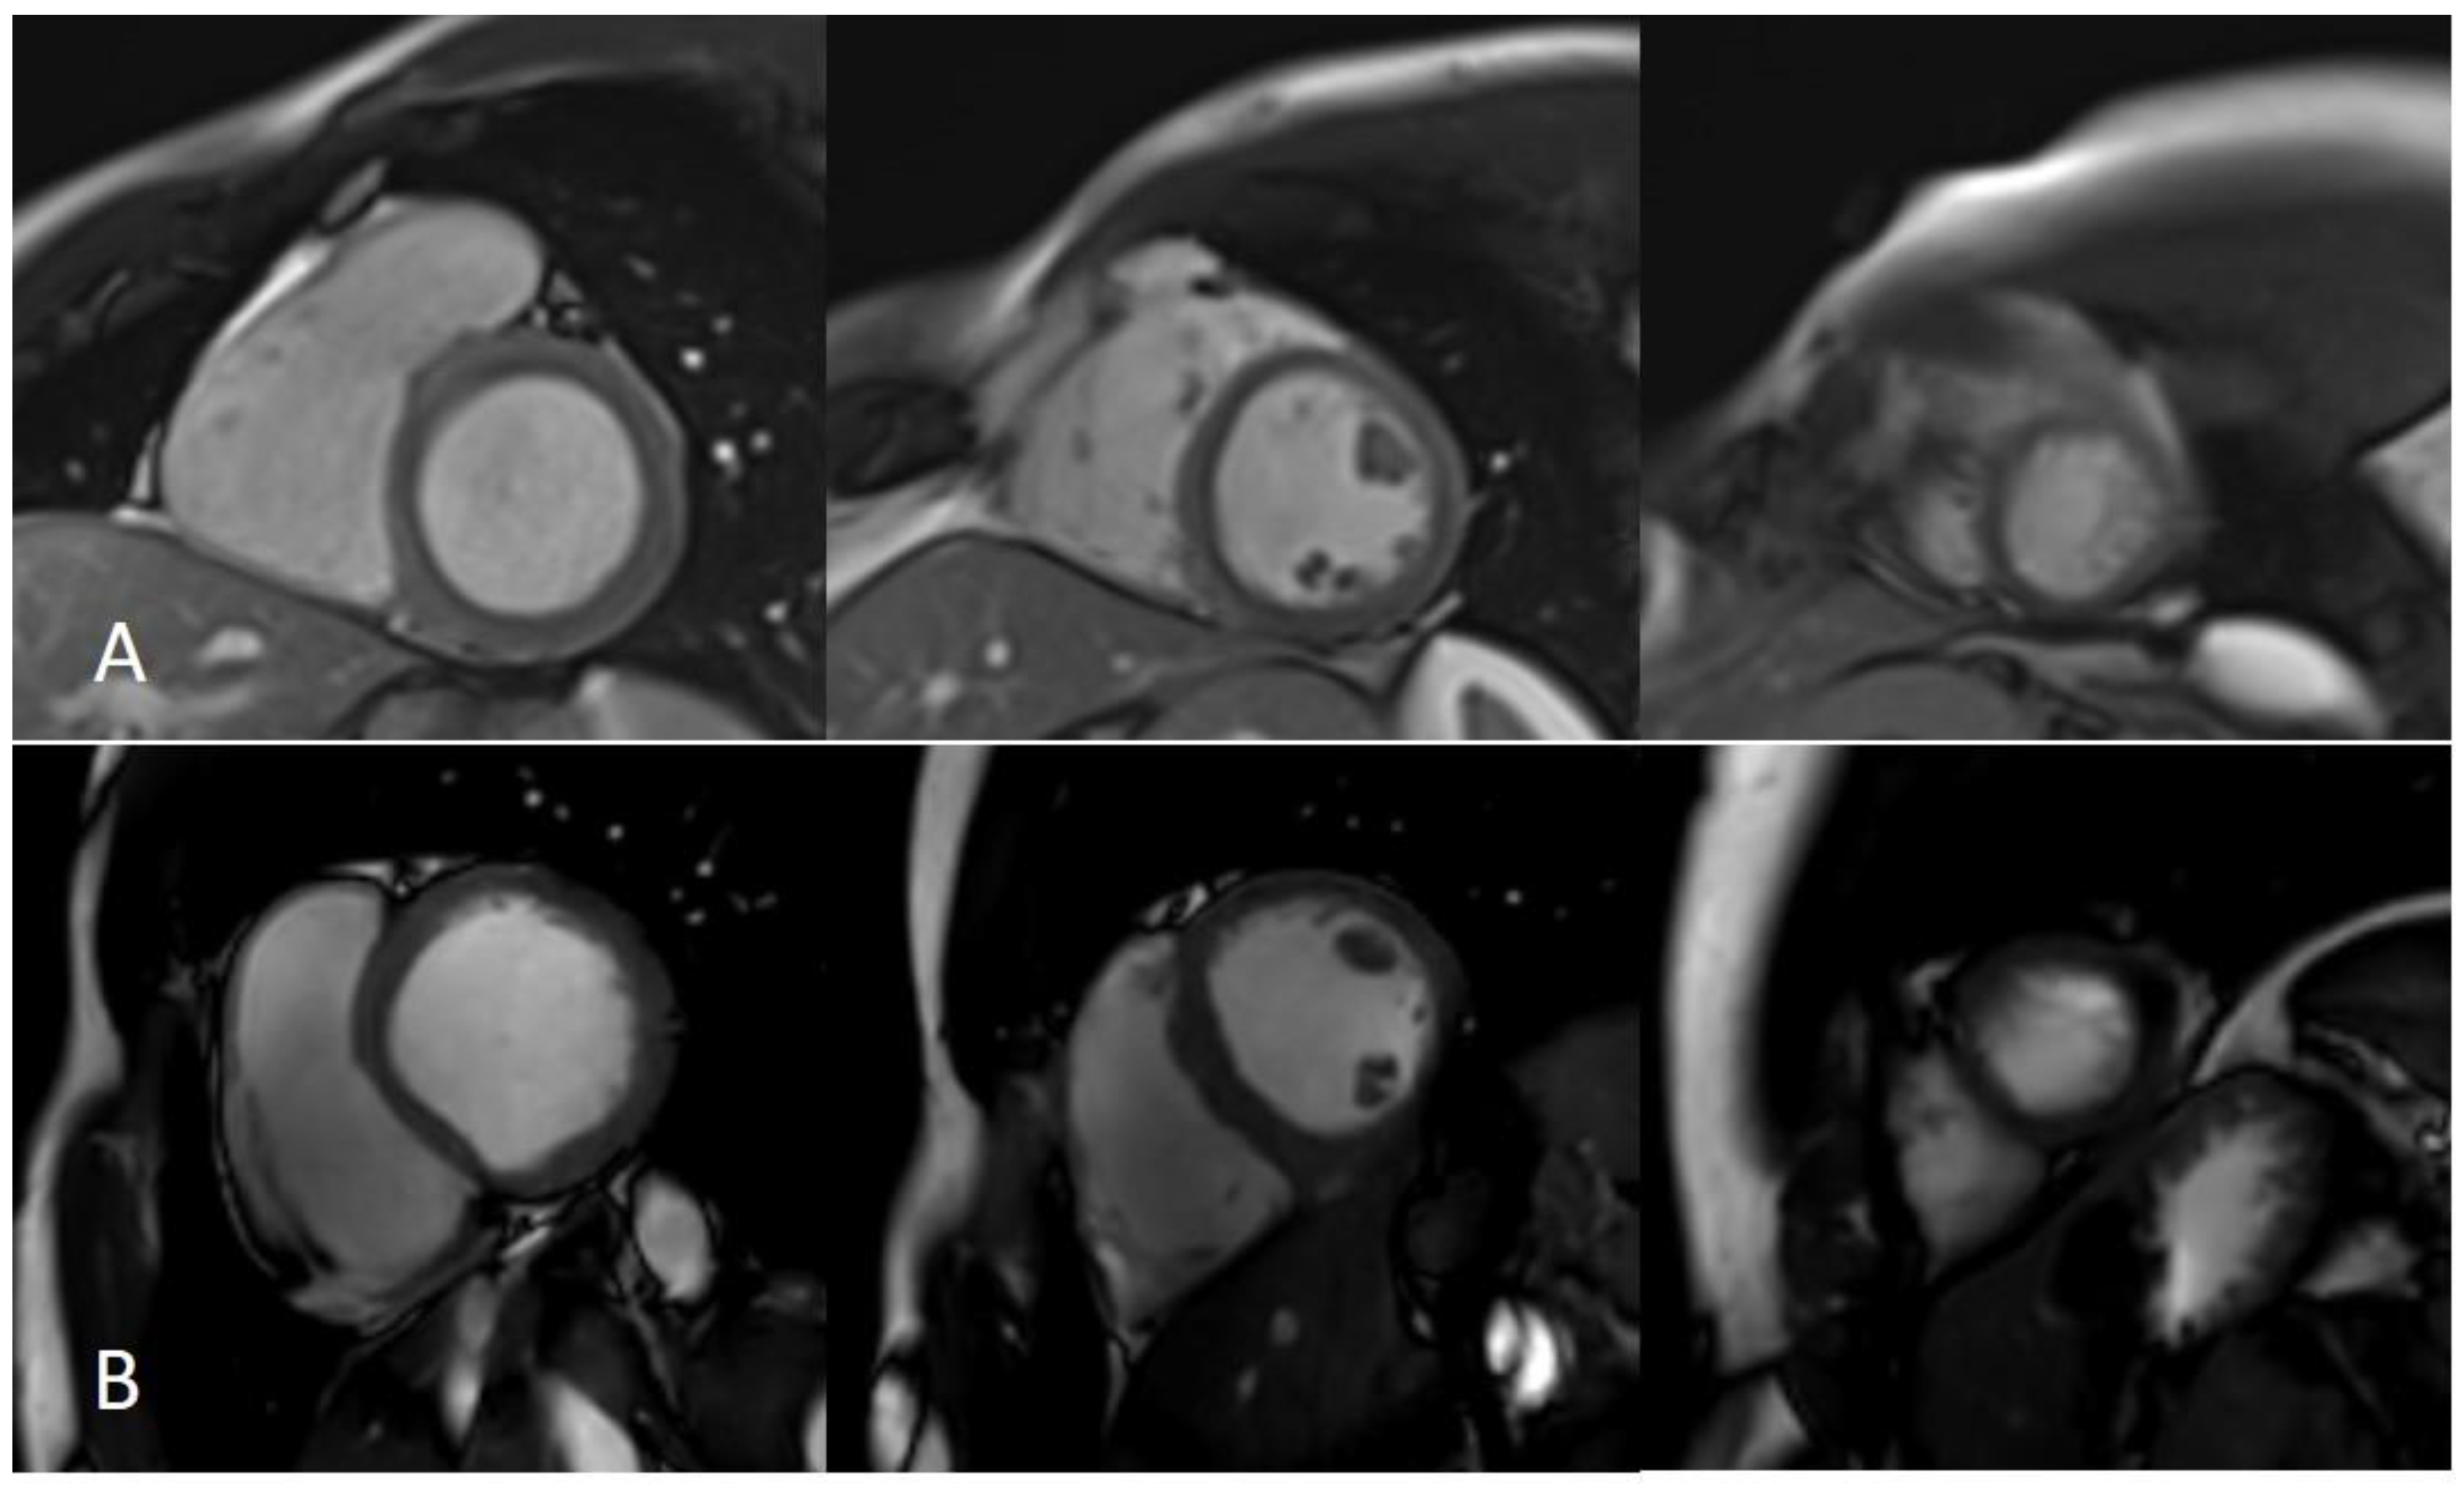

Figure 6.

Artifacts reduction with artificial intelligence implementation. Eighty-two-year-old male patient with previous inferior and inferolateral myocardial infarction. Image (A–C) show the reconstruction of 2D-MSLGE with NR 0% (A), NR 25% (B), and NR 50% (C), respectively. The increasing percentage in NR reconstruction yielded a progressive reduction in image noise in 2D-MSLGE starting from NR 0% (C) and moving through NR 25% (D) and NR 50% (E). A breath artifact characterizing the inferior and inferolateral midapical segments was reduced in the reconstruction in which the 100% artificial intelligence algorithm was applied. In fact, a reduction in quantum noise resulted in better contrast resolution. 2D-MSLGE—2D multisegment late gadolinium enhancement; NR—artificial intelligence reconstruction deep learning noise reduction.